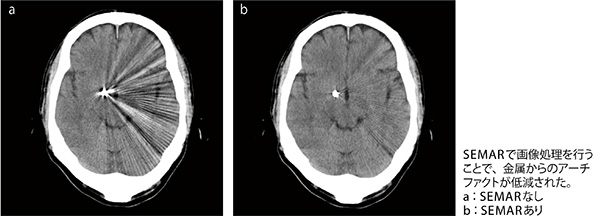

CT検査は、2台を技師2名で担当し3D画像作成まで行う。検査件数は1日約80〜100件。CT担当の赤澤史生主任は、「検査件数が多く、心臓検査や頭部の3D作成などもありますので、看護師や受付のスタッフと協力して進めています」と言う。Aquilion ONE/Global Standard Editionについては、「1回転のボリュームスキャンで高速撮影が行えることから、冠動脈CTや頭部のCT angiography(CTA)、救急などを中心にADCTで検査しています。ワンスキャンによる正確なサブトラクションをはじめ、金属アーチファクト低減技術の“SEMAR”などが可能になり、高画質で効率的な検査が行えるようになりました」と述べる。